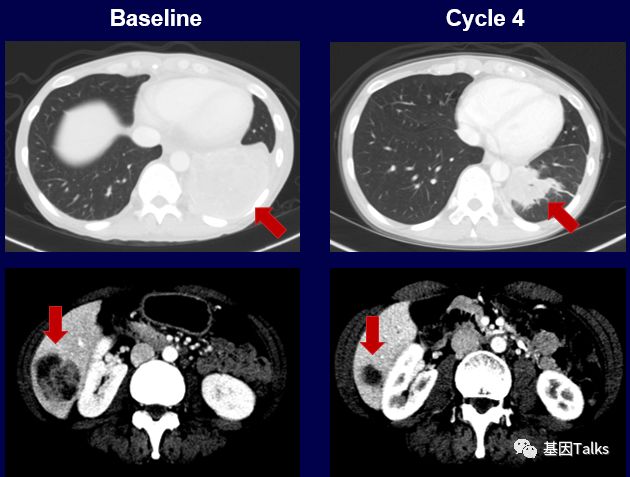

上图上半部分,这位耐药患者尝试LOXO-195新药后,肿瘤再次快速缩小,用药4周后,肿瘤负担减少了38%,继续治疗显示肿瘤负担减少了58%。

上图下半部分显示治疗2周后,新发的耐药突变位点G595R已经检测不到,到目前治疗已经6个月了,治疗效果依然很好,未见有新的耐药位点出现。LOXO-195已经被FDA批准正式开展临床试验,耐药患者有了新希望。